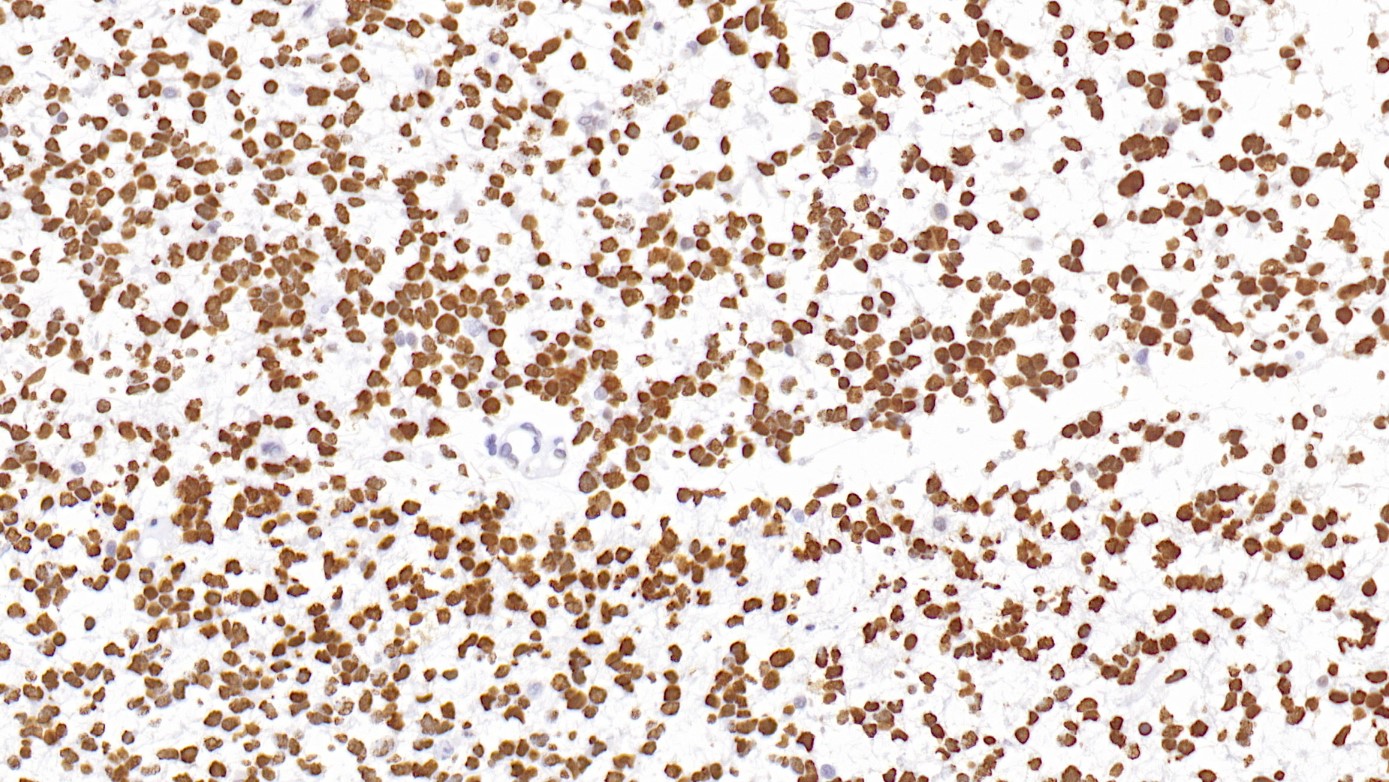

1. Expression of Stathmin and vascular endothelial growth factor C in esophageal cancer and their combined diagnostic value. [J] . Luo Xianghui,Dai Yun,Cao Yanfei. Journal of B.U.ON. : official journal

2. Stathmin/oncoprotein 18, a microtubule regulatory protein, is required for survival of both normal and cancer cell lines lacking the tumor suppressor, p53 [J] . Bruce K. Carney,Lynne Cassimeris.Cancer Biology & Therapy . 2010 (9).

3. Stathmin: a protein with many tasks. New biomarker and potential target in cancer [J] . Barbara Belletti,Gustavo Baldassarre. Expert Opinion on Therapeutic Targets . 2011 (11).